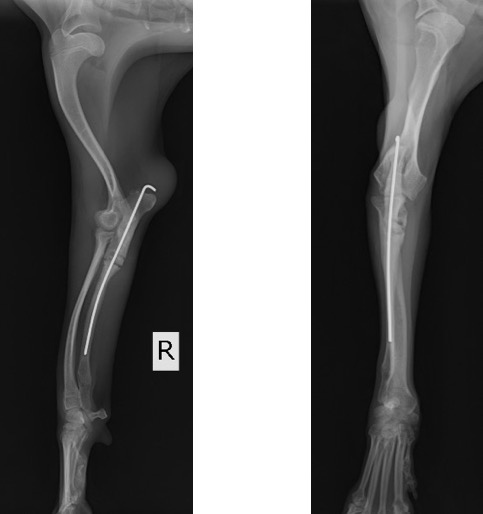

術後のLateral像とAP像 (骨切り後に尺骨のアラインメントを合わせるために髄内ピンとして1.2mm K-wireを刺入しました)